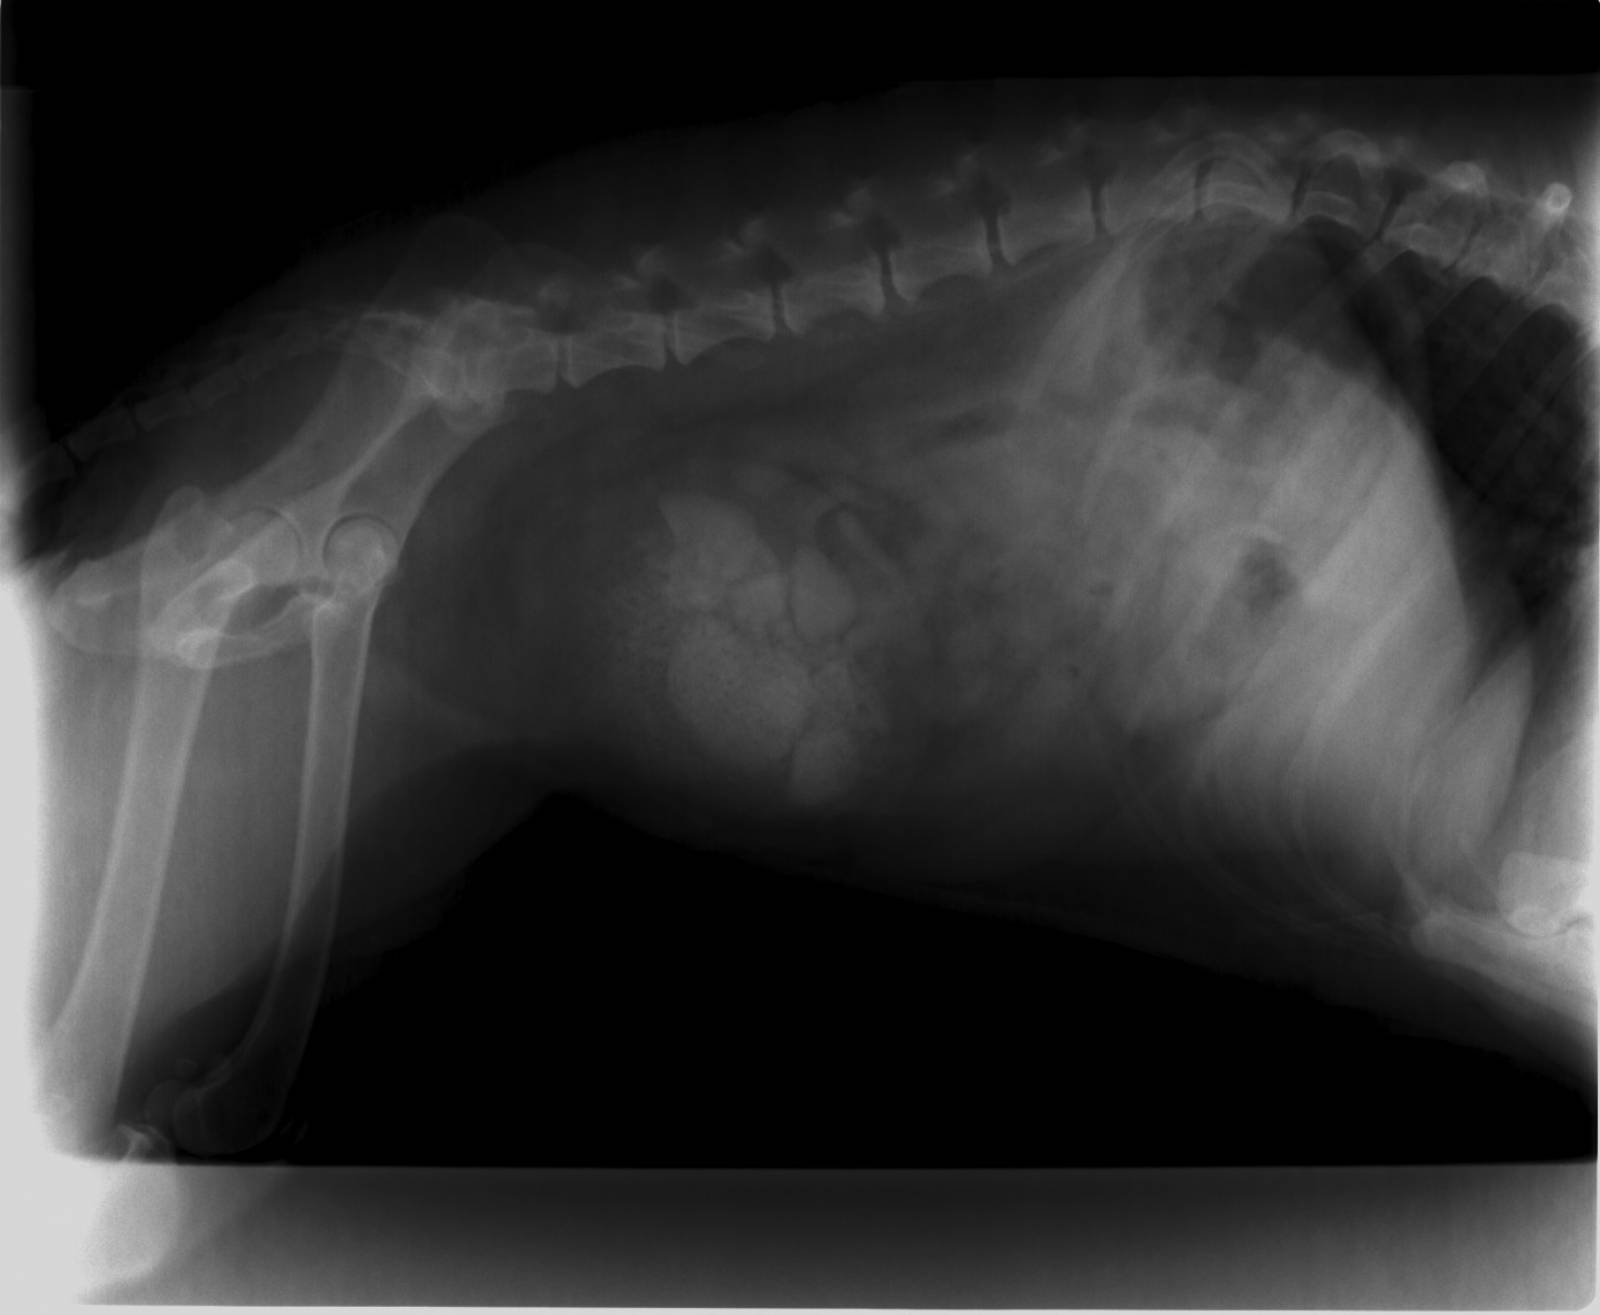

Chirurgies orthopédiques :

fractures

luxations